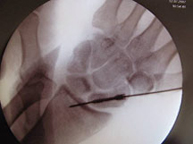

Dentro de la región anatómica de la muñeca se encuentran los huesos del carpo. El hueso escafoides es el que se fractura con más frecuencia tras caídas sobrela mano en extensión. Es por ello una lesión característica en deportes como motociclismo, ciclismo y patín donde se pueden sufrir traumatismos a gran velocidad. El dolor se localiza siguiendo el eje del pulgar pero a nivel de la muñeca y el dolor a la palpación en esta zona (tabaquera anatómica) es extremo. Las fracturas desplazadas se suelen estabilizar quirúrgicamente sin cicatriz,a través de la introducción percutánea de un tornillo intraóseo que permite el inicio de la movilización de la articulación inmediatamente.